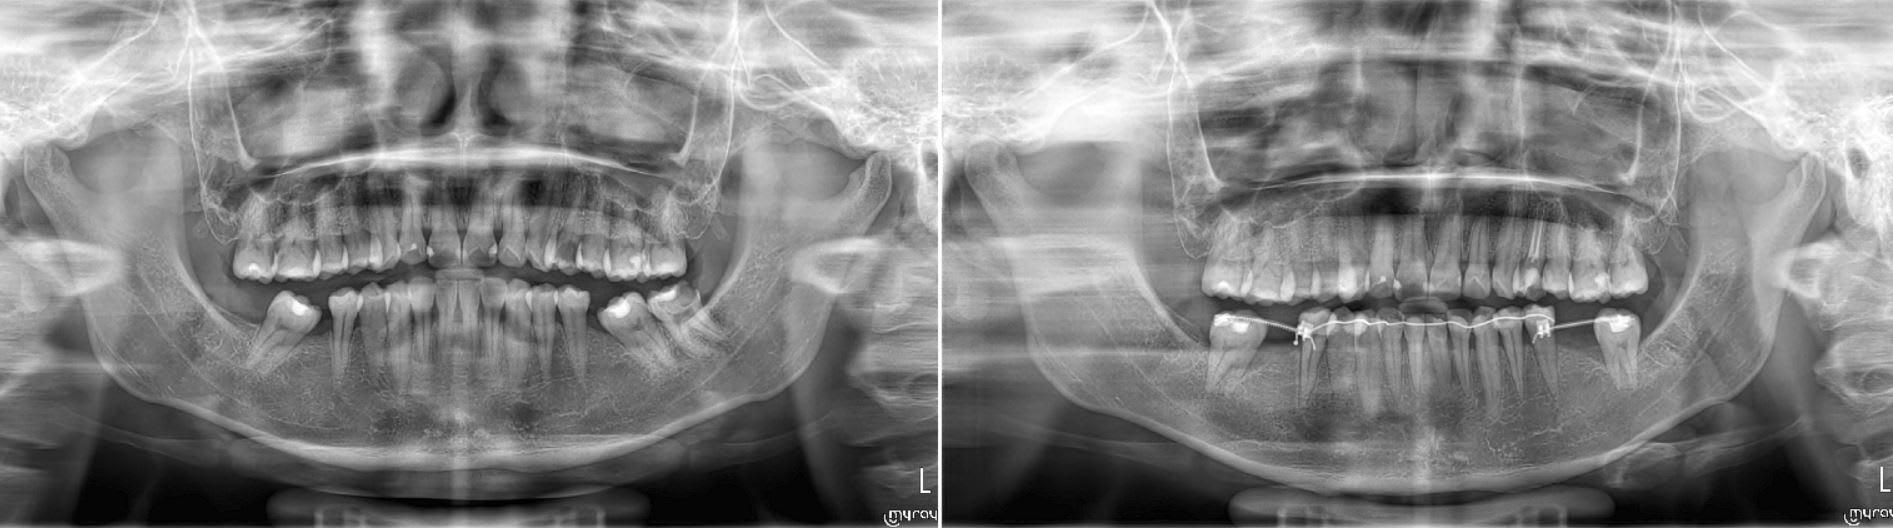

6 mois de traitement.

Patiente disparut depuis plus de deux mois qui à débarqué au cab hier. Direct pano et consultation avec l'implanto.

Je me suis aperçut après son départ que je n'avais pas pris de photo.. Enfin les 7 sont versée en palatale, je corrigerais ça avec deux bracket sur les provisoire des implants.